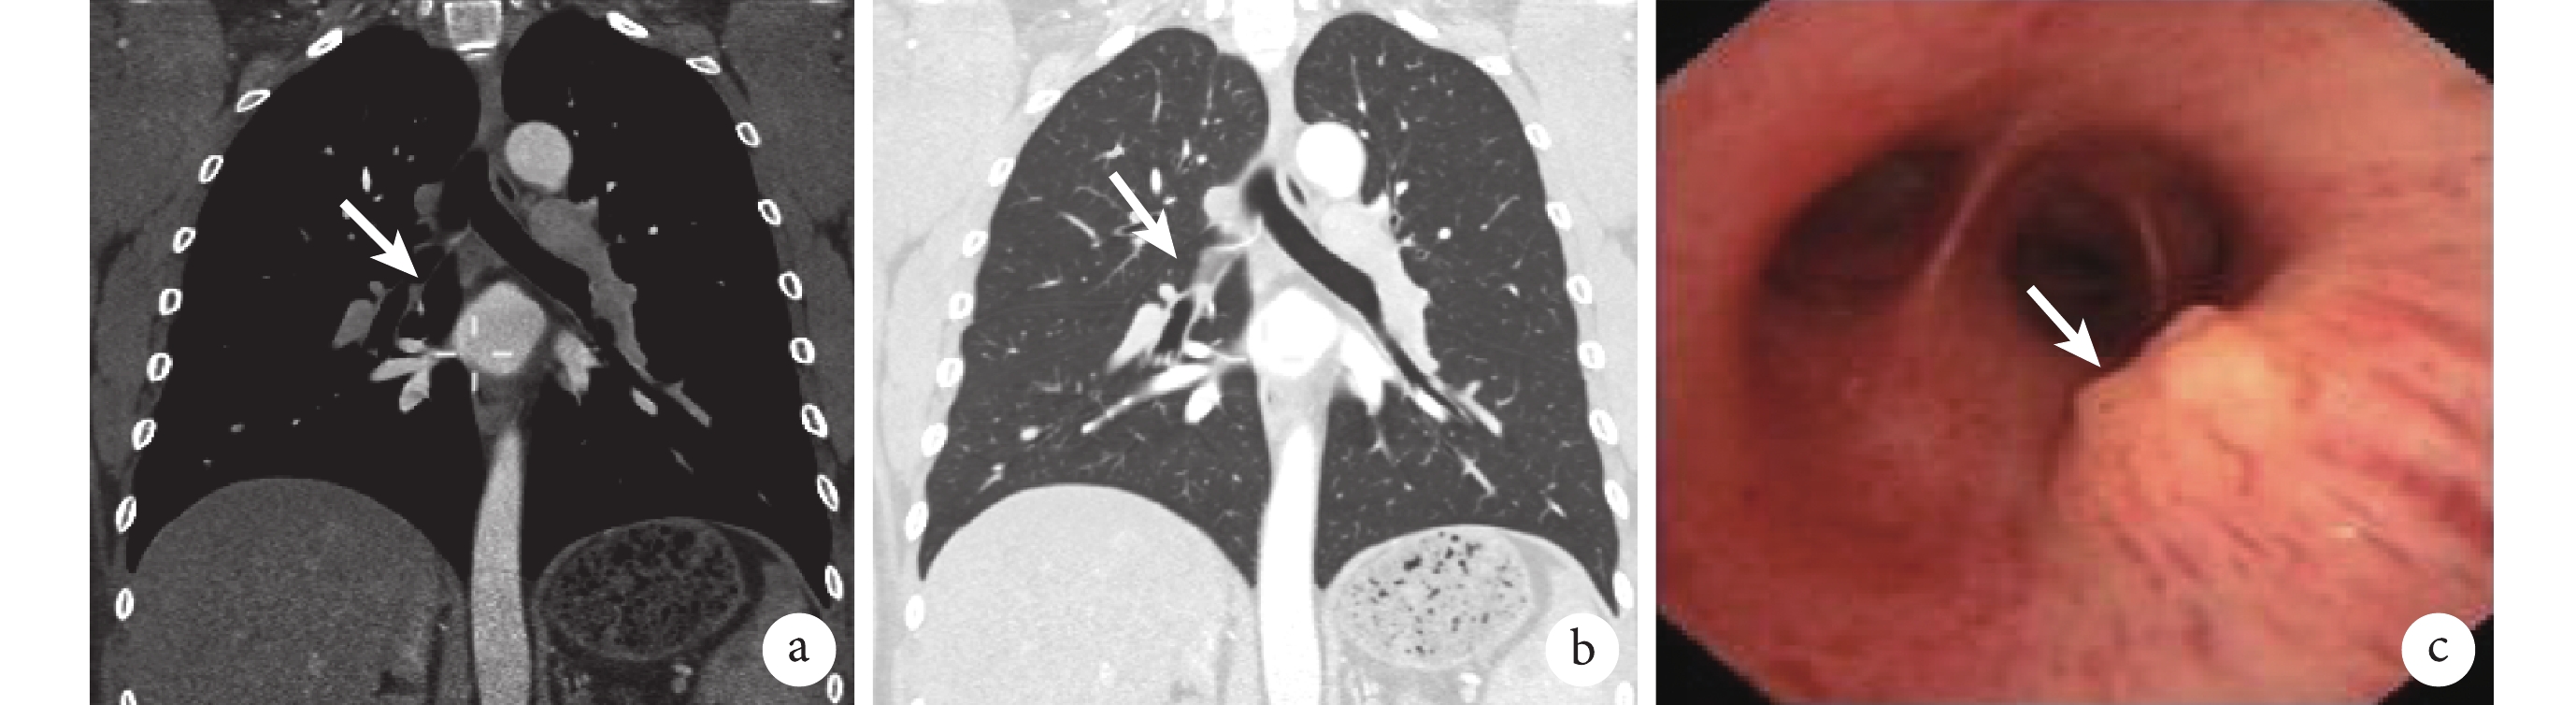

患者男性,40 歲,務農。患者 2 年前無明顯誘因出現咯血,為鮮紅色血痰,量約 5~10 ml/d,間斷咳嗽、咳痰,無其他不適,因癥狀加重曾 2 次于當地醫院給予“抗感染、止血”等治療后好轉。2 d 前無明顯誘因再次出現痰中帶血,為鮮紅色血痰,量約 5 ml,間斷咳嗽、咳痰,于 2017 年 6 月 19 日就診于我院。行雙源 CT 支氣管動脈血管成像示雙側支氣管動脈未見明顯異常,右肺中葉部分膨脹不全(圖 1a、b)。門診以“咯血原因待查”收入院。既往“慢性支氣管炎”病史 10 余年,“高血壓”病史 2 年,均未規律治療。

a、b. 雙側支氣管動脈血管成像未見明顯異常,右肺中葉部分膨脹不全(白箭);c.右肺中間段支氣管管壁息肉樣新生物,表面可見血管(白箭)

入院后輔助檢查:血尿便常規、凝血常規、腫瘤標志物(CEA、NSE、CYFRA21-1)、痰濃縮集菌真菌涂片、細菌涂片、抗酸桿菌涂片、痰培養及藥敏試驗、1,3-β-D 葡聚糖試驗、半乳甘露聚糖試驗均在正常范圍。2017 年 6 月 24 日行電子支氣管鏡檢查,鏡下見右肺中間段支氣管管壁息肉樣新生物,表面可見血管(圖 1c)。對新生物行鉗夾及毛刷檢查,蘇木精-伊紅(HE)染色,光鏡下見支氣管黏膜下相對大的圓形和卵圓形細胞,邊界清楚,有豐富的顆粒狀胞漿,細胞核小圓形,偏心、缺乏核仁,無非典型性、壞死、出血等。部分被覆蓋的支氣管上皮鱗狀化生。病理報告示顆粒細胞瘤。免疫組織化學:S-100 蛋白陽性,簇分化抗原 68(CD68)陽性,細胞角蛋白(cytokeratin,CK)陰性,增殖細胞核抗原(Ki-67)<2%,波形蛋白(vimentin,Vim)陽性(圖 2)。